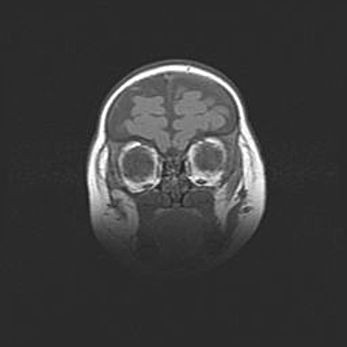

Лейкомаляция с кистозно-глиозной дегенерацией головного мозга.

Возраст: 2 месяца 25 дней

Вес: 6400 г

Окружность головы: 40 см

Срок гестации: 41 неделя

Лейкомаляцию относят к ишемически-гипоксическим повреждениям головного мозга, диагностируемым у новорожденных. При лейкомаляции в головном мозге обнаруживают очаги некроза, возникшие после тяжелой гипоксии и нарушения кровотока. В процессе морфогенеза очаги проходят три стадии: 1) развития некроза, 2) резорбции и 3) формирования глиозного рубца или кисты. Перивентрикулярная лейкомаляция (ПЛ) встречается примерно в 12% случаев среди новорожденных, обычно – у недоношенных детей, причем, частота ее зависит от массы, с которой младенец появился на свет. Наибольшее число малышей страдает лейкомаляцией, если масса при рождении 1500-2500 г.